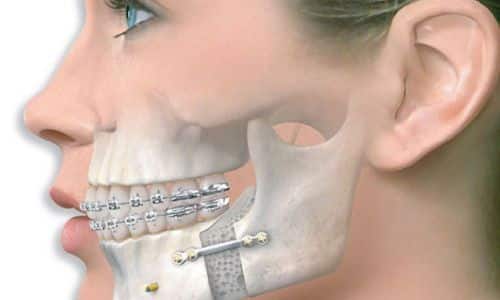

3.2. Phẫu Thuật Nha Khoa

Khi nhiễm trùng đã nghiêm trọng, phẫu thuật có thể cần thiết để làm sạch khu vực bị ảnh hưởng và giúp phục hồi hoàn toàn.

3.2.3. Phẫu Thuật Loại Bỏ Mô Viêm

Trong một số trường hợp, phẫu thuật để loại bỏ mô viêm xung quanh vùng xương hàm bị nhiễm trùng là không thể tránh khỏi.

4.Phòng Tránh Nhiễm Trùng Xương Hàm Sau Phẫu Thuật: Những Điều Cần Lưu Ý

Sau khi trải qua một ca phẫu thuật nha khoa, xương hàm giống như một “vùng đất mới được khai phá”, đang trong giai đoạn nhạy cảm nhất của quá trình phục hồi. Tuy nhiên, chính lúc này cũng là lúc mà nhiễm trùng dễ dàng tấn công hơn bao giờ hết. Để bảo vệ “vùng đất” quý giá này, bạn cần có những biện pháp phòng ngừa chặt chẽ để đảm bảo xương hàm có thể lành lại một cách an toàn và khỏe mạnh. Dưới đây là những điều cần lưu ý để phòng tránh nhiễm trùng xương hàm sau phẫu thuật.